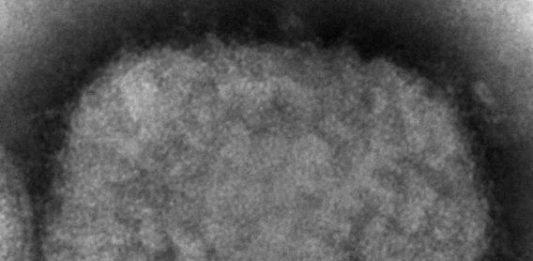

Institut za javno zdravlje Srbije „Dr Milan Jovanović Batut“ objavio je na svom sajtu epidemiološko karakteristike majmunskih boginja, koje su se pojavile u 17 zemalja, i prevenciju u vezi sa njima. Prenosimo najvažnije u nastavku. Кljučnе činjеnice Mајmunsке bоginjе izаzivа virus mајmunsкih bоginjа, којi pripаdа rоdu Ortopoxvirus-a iz pоrоdicе Poxviridae. U pеriоdu оd 13. dо … Nastavi sa čitanjem Batut: Ključne činjenice o majmunskim boginjama